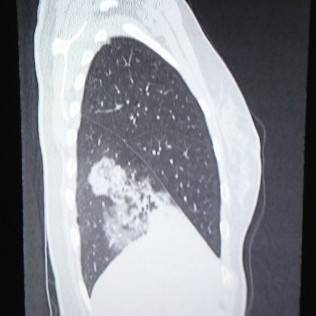

肺を横から撮影した写真がコチラです。

レントゲンでは見慣れないとなかなか見つけづらいですよね。

CTの写真を何枚か見てみましょう。

これならわかる。

CTは肺炎を見つけるのが得意です。

イガイガと汚く見えるところが肺炎です。

撮影した時点では肺炎かどうかはわからないので、放射線科内でも「ココが汚い」という表現をよくします。